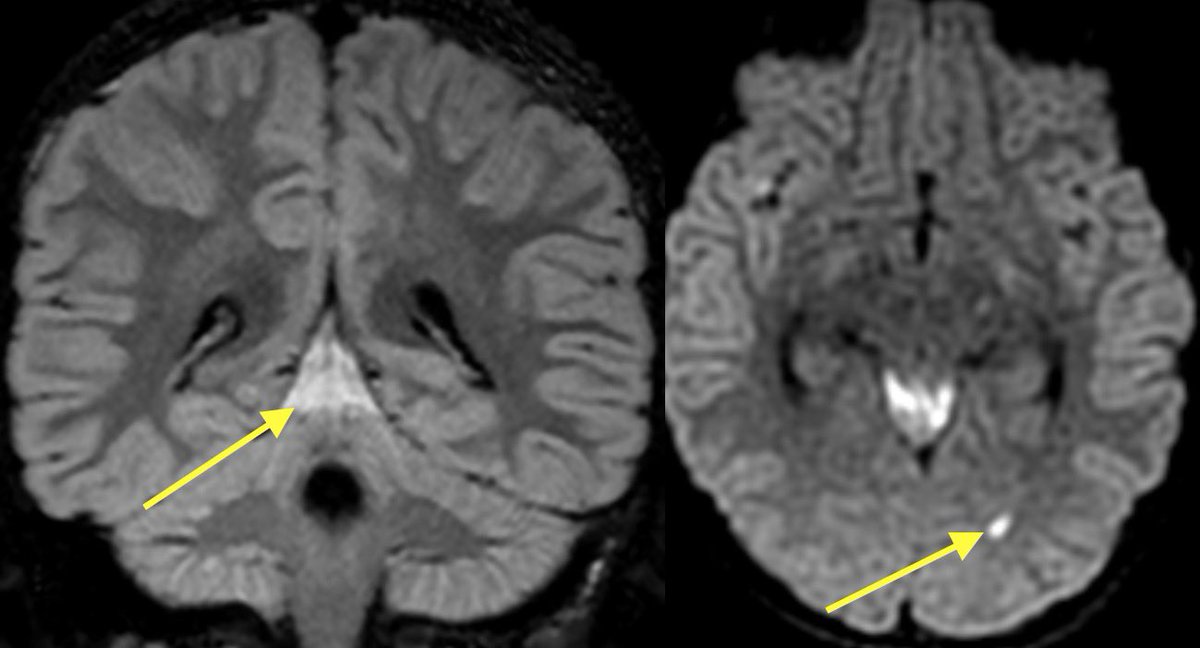

💡 When concerned for cholesteatoma make sure to get the NON ECHO PLANAR DWI to reduce artifact around the T bone which increases sensitivity for cholesteatoma. Cholesteatomas are very bright on DWI (think of them as extracranial epidermoid cysts)

1️⃣DWI shows restricted diffusion of the left mastoid air cells (can be seen in cholesteatoma or purulent mastoiditis)

2️⃣However, additional restriction, enhancement, and loss of normal CSF signal in the left IAC was highly suggestive of suppurative Labyrinthitis

Cholesteatoma with superimposed infection was also complicated by meningitis (seen best at quadrigeminal plate cistern), ventriculitis, skull base osteomyelitis (petrous apicitis) and probably some other itisis that I’m forgetting